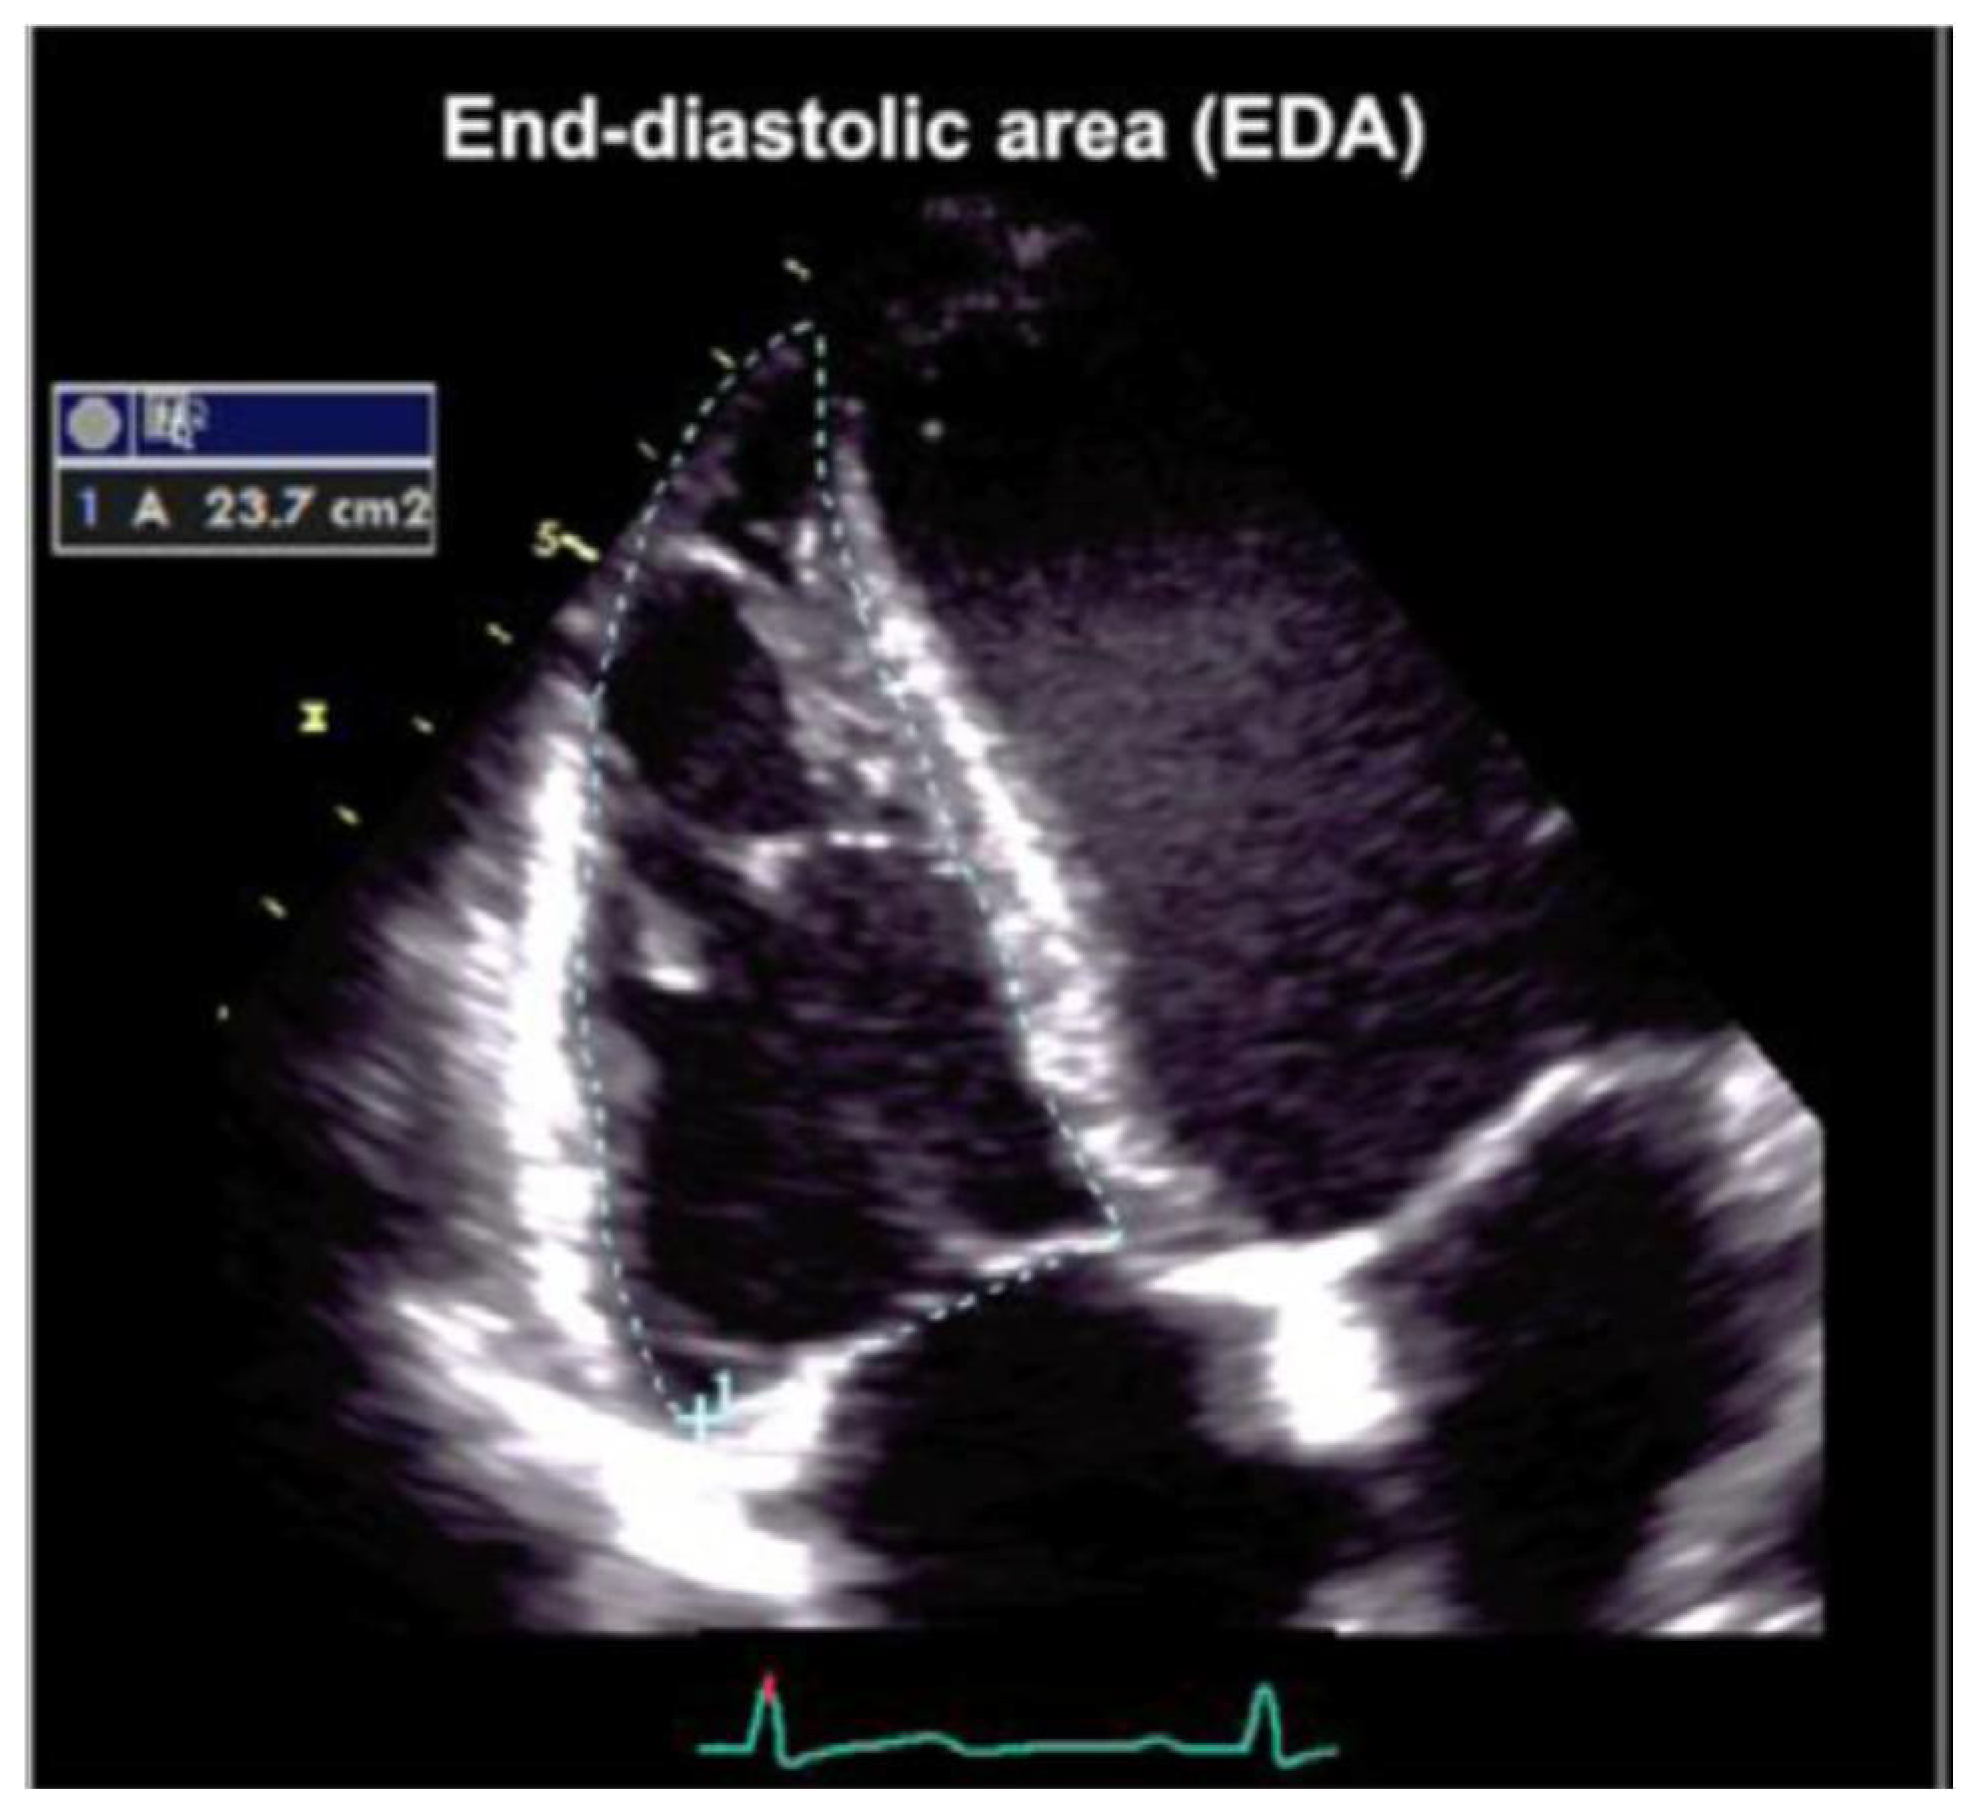

7. Echocardiographic Assessment

| Parameter | Pathological Values | Normal Range |

|---|---|---|

| RV Area Change | Fractional Area Change <33 | >40% |

| RVOT PLAX diameter | >33 mm | 20–30 mm |

| RVOT prox diameter | >36 mm | 21–35 mm |